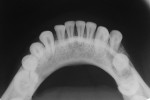

Nineteen patients between the ages 3 and 12 years with maxillofacial injuries (Figure 1 and Figure 2) presented to the Department of Pedodontics and Preventive Dentistry in K D Dental College and Hospital, Mathura, India. Detailed case histories, clinical examinations, and radiographic investigations such as orthopantomography, occlusal radiography, and intraoral periapical radiography were performed (Figure 3 through Figure 8). After careful evaluation, a diagnosis of the type of fracture was made and a treatment plan was formulated for each patient. Informed consent was obtained from the parent, and in some cases, treatment was performed under general anesthesia, with written consent obtained from the parent.

In all patients, splints and arch bars were removed after 2 to 4 weeks. Postoperative radiographs were obtained to confirm the healing of the fractured site before removal of the splint (Figure 5 and Figure 8), and all the patients were followed-up for 12 months. None of the patients had complications in the postoperative period, and uneventful healing and union of the fracture segment occurred in all patients. In one patient, healing time was prolonged because of continuous dislodgement of the splint, which was re-cemented. A slight discrepancy in the occlusion in a few patients was observed, which was corrected on its own over the course of time.